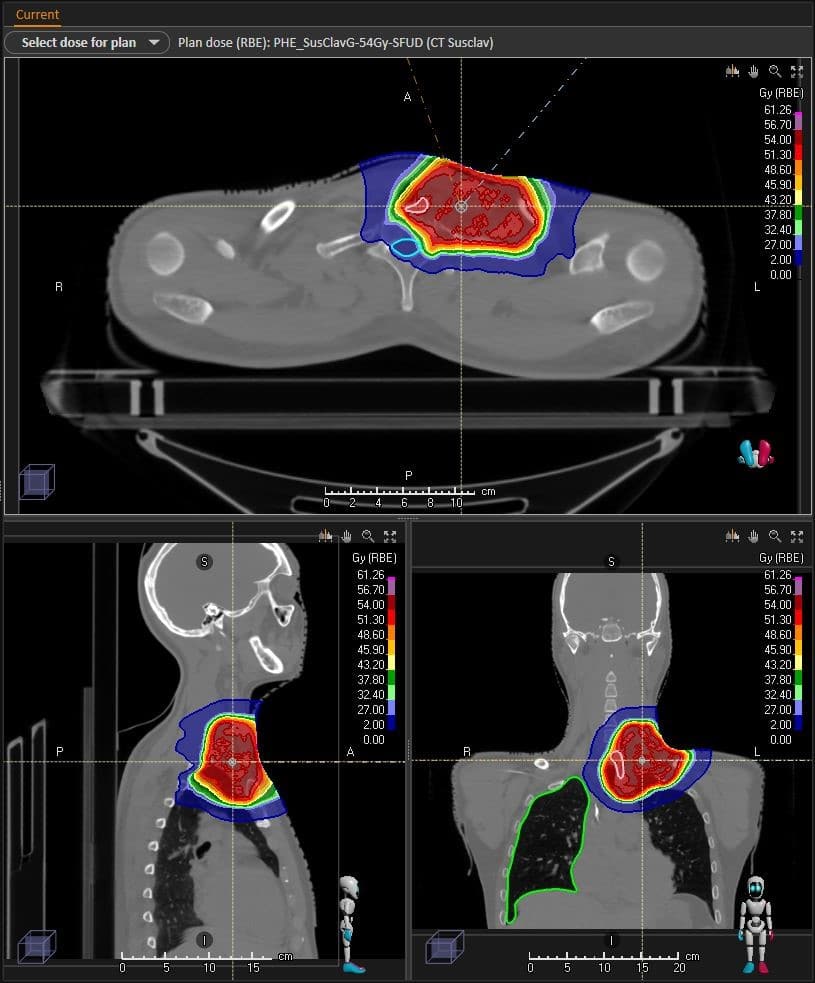

Grâce au soutien du Département des Alpes-Martimes, de la Coplay May Foundation, de la Fondation Flavien et de donateurs privés, le Centre Antoine Lacassagne a été le premier établissement en France à pouvoir traiter par protonthérapie un patient atteint d’une tumeur cervicale rare proche de la clavicule grâce au système Cone Beam CT (CBCT) : un mini-scanner 3D intégré à l’accélérateur Proteus®One (tous deux développés par la société IBA) remplaçant l’ancien système de radiographies classiques. « Cette technologie très innovante permet d’avoir une bien meilleure qualité d’image, de repositionner précisément chaque jour ce patient avant la délivrance de son traitement et de lui épargner une irradiation, même minime, d’une partie du poumon et de la thyroïde, organes à proximité de la lésion. » souligne Marie VIDAL, Physicienne Médicale en charge du projet au Centre Antoine Lacassagne.

« Le CBCT élargit les indications de traitement par protonthérapie », explique le Dr Jérôme DOYEN, Radiothérapeute, Responsable de l’Institut Méditerranéen de Protonthérapie. « Cette technologie rend possible l’irradiation de tumeurs ORL par protonthérapie en permettant de mieux protéger l’œsophage, les muscles de la déglutition, l’os et les glandes produisant la salive. Elle permettra également le traitement de tumeurs mobiles, thoraciques, abdominales et pelviennes, grâce à la possibilité de vérifier beaucoup plus précisément la position des organes les uns par rapport aux autres. Elle pourra s’appliquer à beaucoup de tumeurs pédiatriques (medulloblastomes, néphroblastomes et neuroblastomes de l’enfant) mais aussi à certaines tumeurs chez l’adulte jeune. »